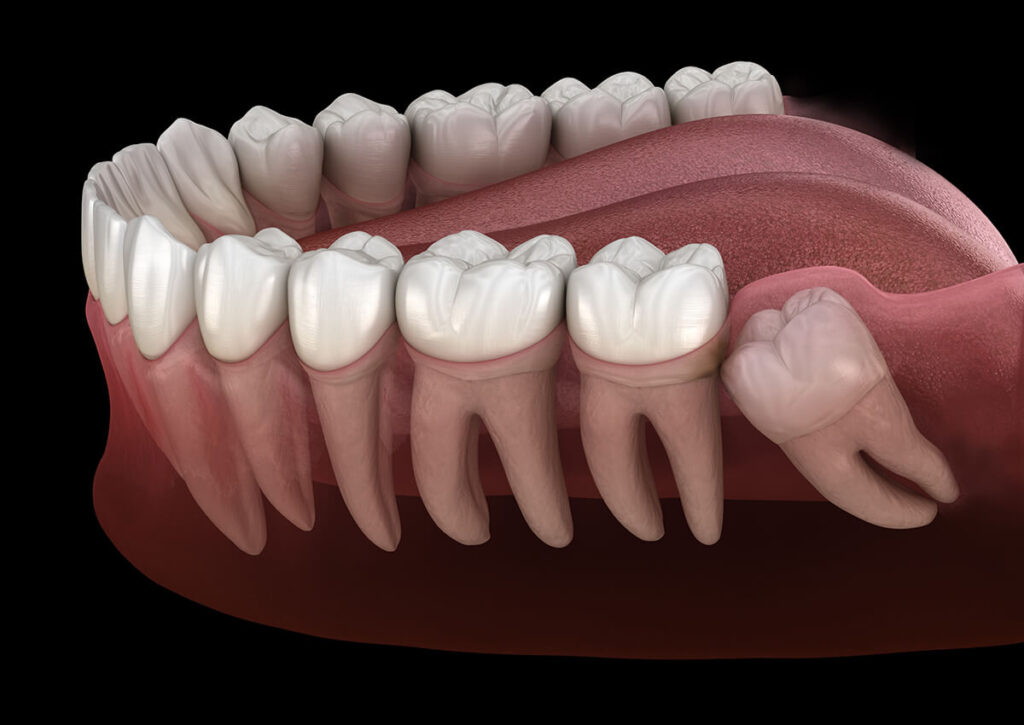

دندان های عقل (مولر سوم) آخرین دندان هایی هستند که در فک رشد می کنند و به دلیل کمبود فضا، زاویه نامناسب و موانع استخوانی یا بافت نرم ممکن است در مسیر رشد طبیعی قرار نگیرند. این وضعیت بهعنوان «دندان عقل نهفته» شناخته می شود. شیوع دندان عقل نهفته بالا است و معمولاً به دلیل رویش دندان عقل در سنین ۱۷ تا ۲۵ سالگی رخ می دهد. علل نهفتگی ممکن است به دلیل موارد زیر باشد:

جراحی دندان عقل نهفته نیازمند تجربه، تشخیص دقیق و انتخاب ابزار مناسب برای کاهش عوارضی مانند درد، تورم، تحلیل استخوان و آسیب عصبی است.